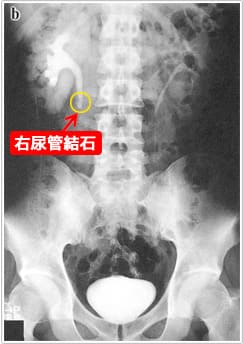

2) X線および超音波検査(当クリニックで施行できます)

尿路結石が疑われる患者の画像初回評価としては腹部超音波検査(図3)と腎から膀胱部まで含めた腹部単純X線撮影 (kidney, ureter, bladder : KUB)(図4)を行います。

これだけで結石の局在診断としては十分な場合もあります。